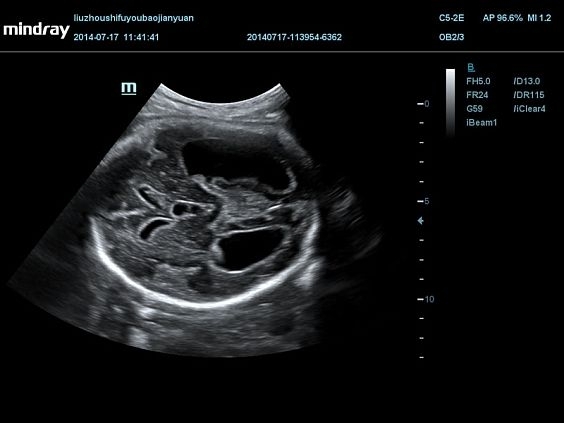

Изображения

Универсальные, Кардиологические, Гинекологические, Педиатрические, 3D/4D акушерство